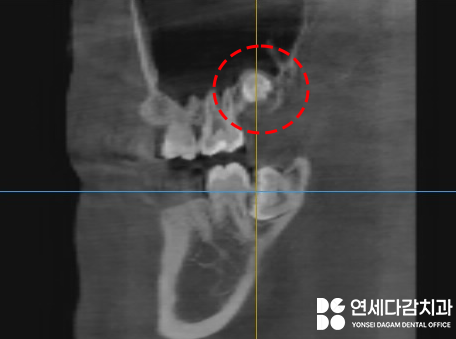

따라서 CT 촬영을 통해

3차원적인

구조를 분석해 봤습니다.

CT 분석 결과,

잇몸 밖으로 맹출 되어 있던 것은

제3대구치 근처에 정상 개수보다

하나 더 생긴 과잉치이면서,

정상 크기보다 작은 형태인

왜소치였습니다.

실제 일반적인 크기의 제3대구치는

양쪽 다 과잉치 아래쪽으로

더 깊숙이 매복되어 있었습니다.